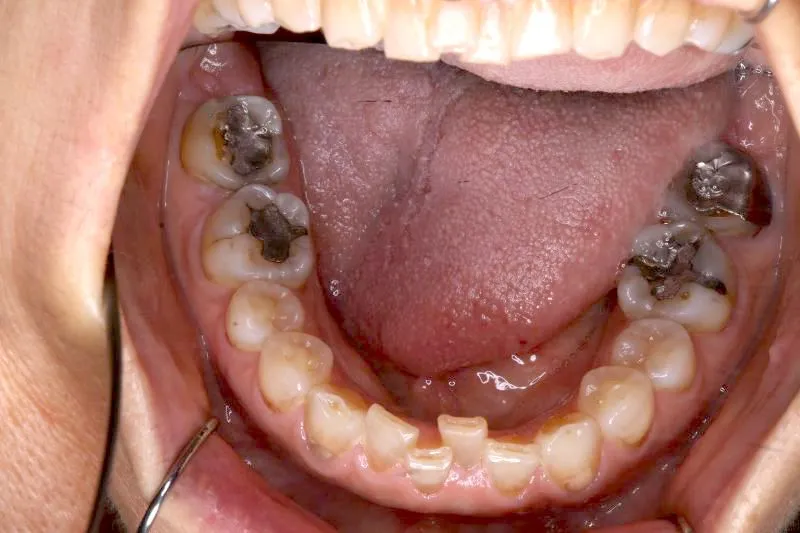

2.診断名あるいは主な症状 空隙歯列・先天性欠損歯

上の歯が2本足りないため上下のアーチが合わず、下の歯がガタガタになっています。

上下の幅をあわせ、噛み合わせから調整していきます。